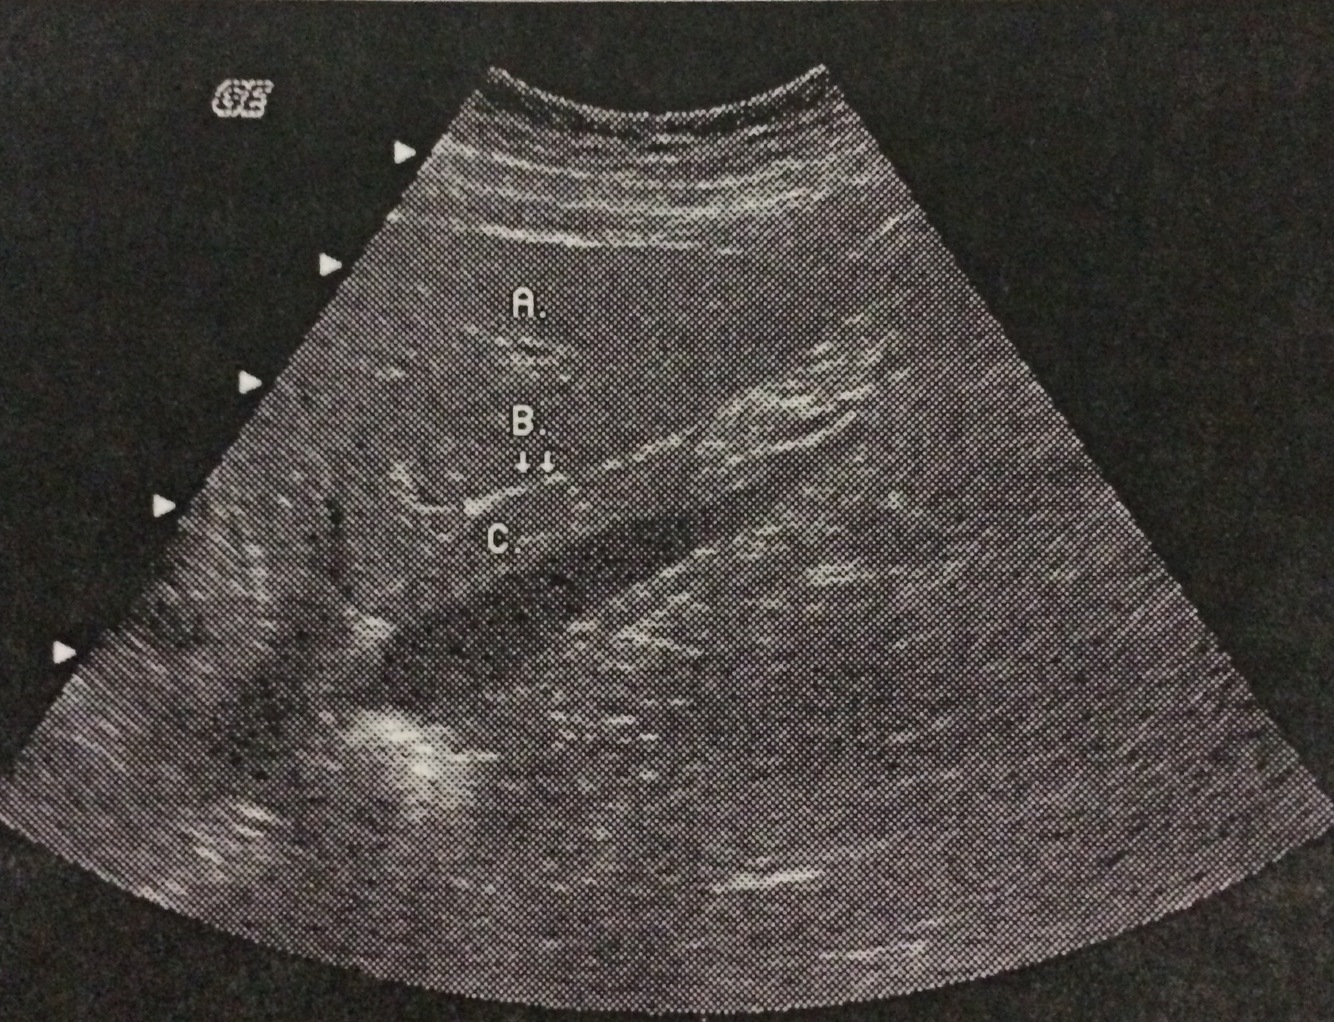

What lobe of the liver does the letter A represent?

Left lobe

What structure does the letter B represent?

Ligamentum venosum

What lobe of the liver does the letter C represent?

Caudate lobe